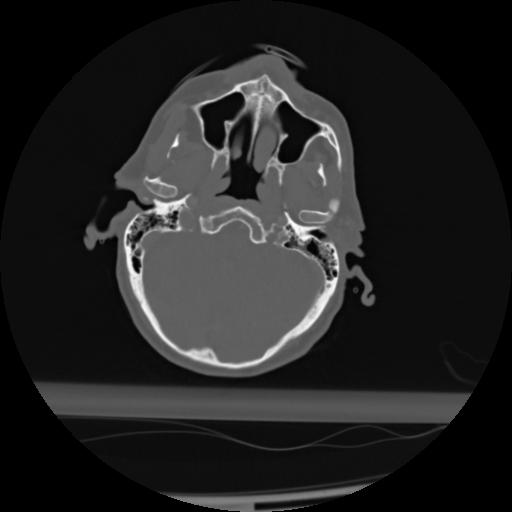

21 ANGIO,CE,Axial,3.0,ANGIO,,